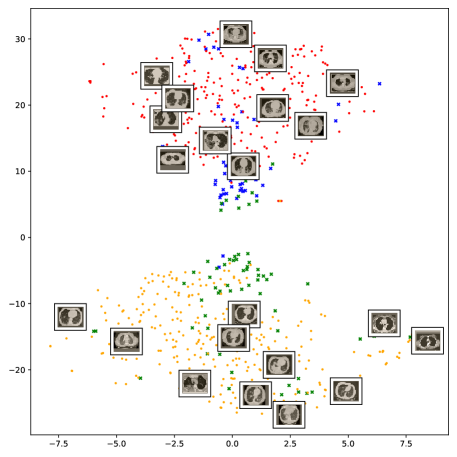

In order to provide better explainability of the deep models and making them more transparent we apply two visualization techniques. The first approach is the t-distributed Stochastic Neighboring Embedding (t-SNE) [13], which is a dimensionality reduction and visualization technique for visualizing clusters of instances in a high-dimensional space. The obtained visualizations of the t-SNE embeddings show well-separated clusters representing CT images for COVID-19 and Non-COVID-19 cases. The second approach is the Gradient-weighted Class Activation Mapping (Grad-CAM) [14], which is a visualization technique for CNN-based models. It provides high-resolution and class-discriminative visualizations that localize the important image regions considered for the model prediction. The Grad-CAM visualizations show how accurately our models localize the COVID-19 associated regions. Overall, this paper exhibits the following contributions:

5.5.1 The t-SNE visualization

To understand how the deep neural networks represent the CT images in the high-dimensional feature space we apply the t-SNE algorithm to visualize these features. For each image in the SARS-CoV-2 dataset we first extract the 2048-dimensional feature vector from the penultimate layer of the Inception V3 model. Next, we apply t-SNE to map the features on to 2D space and then visualize the embeddings of training and test representations. Figure 11 clearly shows two well-separated clusters of the CT images of COVID-19 and Non-COVID-19. This indicates that the distribution of training and test features are quite similar to each other, which indicates good generalization capabilities of our model. The clear and wide margin between the two classes shows how nicely the CT images are separated in feature space.

We also repeat the same procedure for the COVID19-CT dataset. The feature vectors are extracted from the penultimate layer of the DenseNet169 model. The length of the feature vectors is 1664 dimensions. We again apply t-SNE to map the features on to 2D space to explore and visualize them. Figure 12 shows two clusters representing CT images for the COVID-19 and Non-COVID-19 classes. Even though the classes are fairly distinguishable with a clear decision boundary, however, we can see that some CT images are misclassified, and more specifically the Non-COVID-19 CT images from the test set.